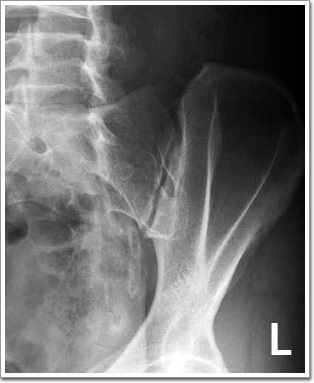

S-I Joint

Inflammatory Change, Fusion 등을 관찰한다.

환자는 Supine Position을 취한다. 촬영 측Pelvis25~30° 정도 Elevate 시키고 Table의 MidlineASIS에서 Medial로 1인치 되는 점과 일치하도록 한다.

Ilium의 반측면상이 나타나며 , S-I joint가 한면에 나타내야 한다.